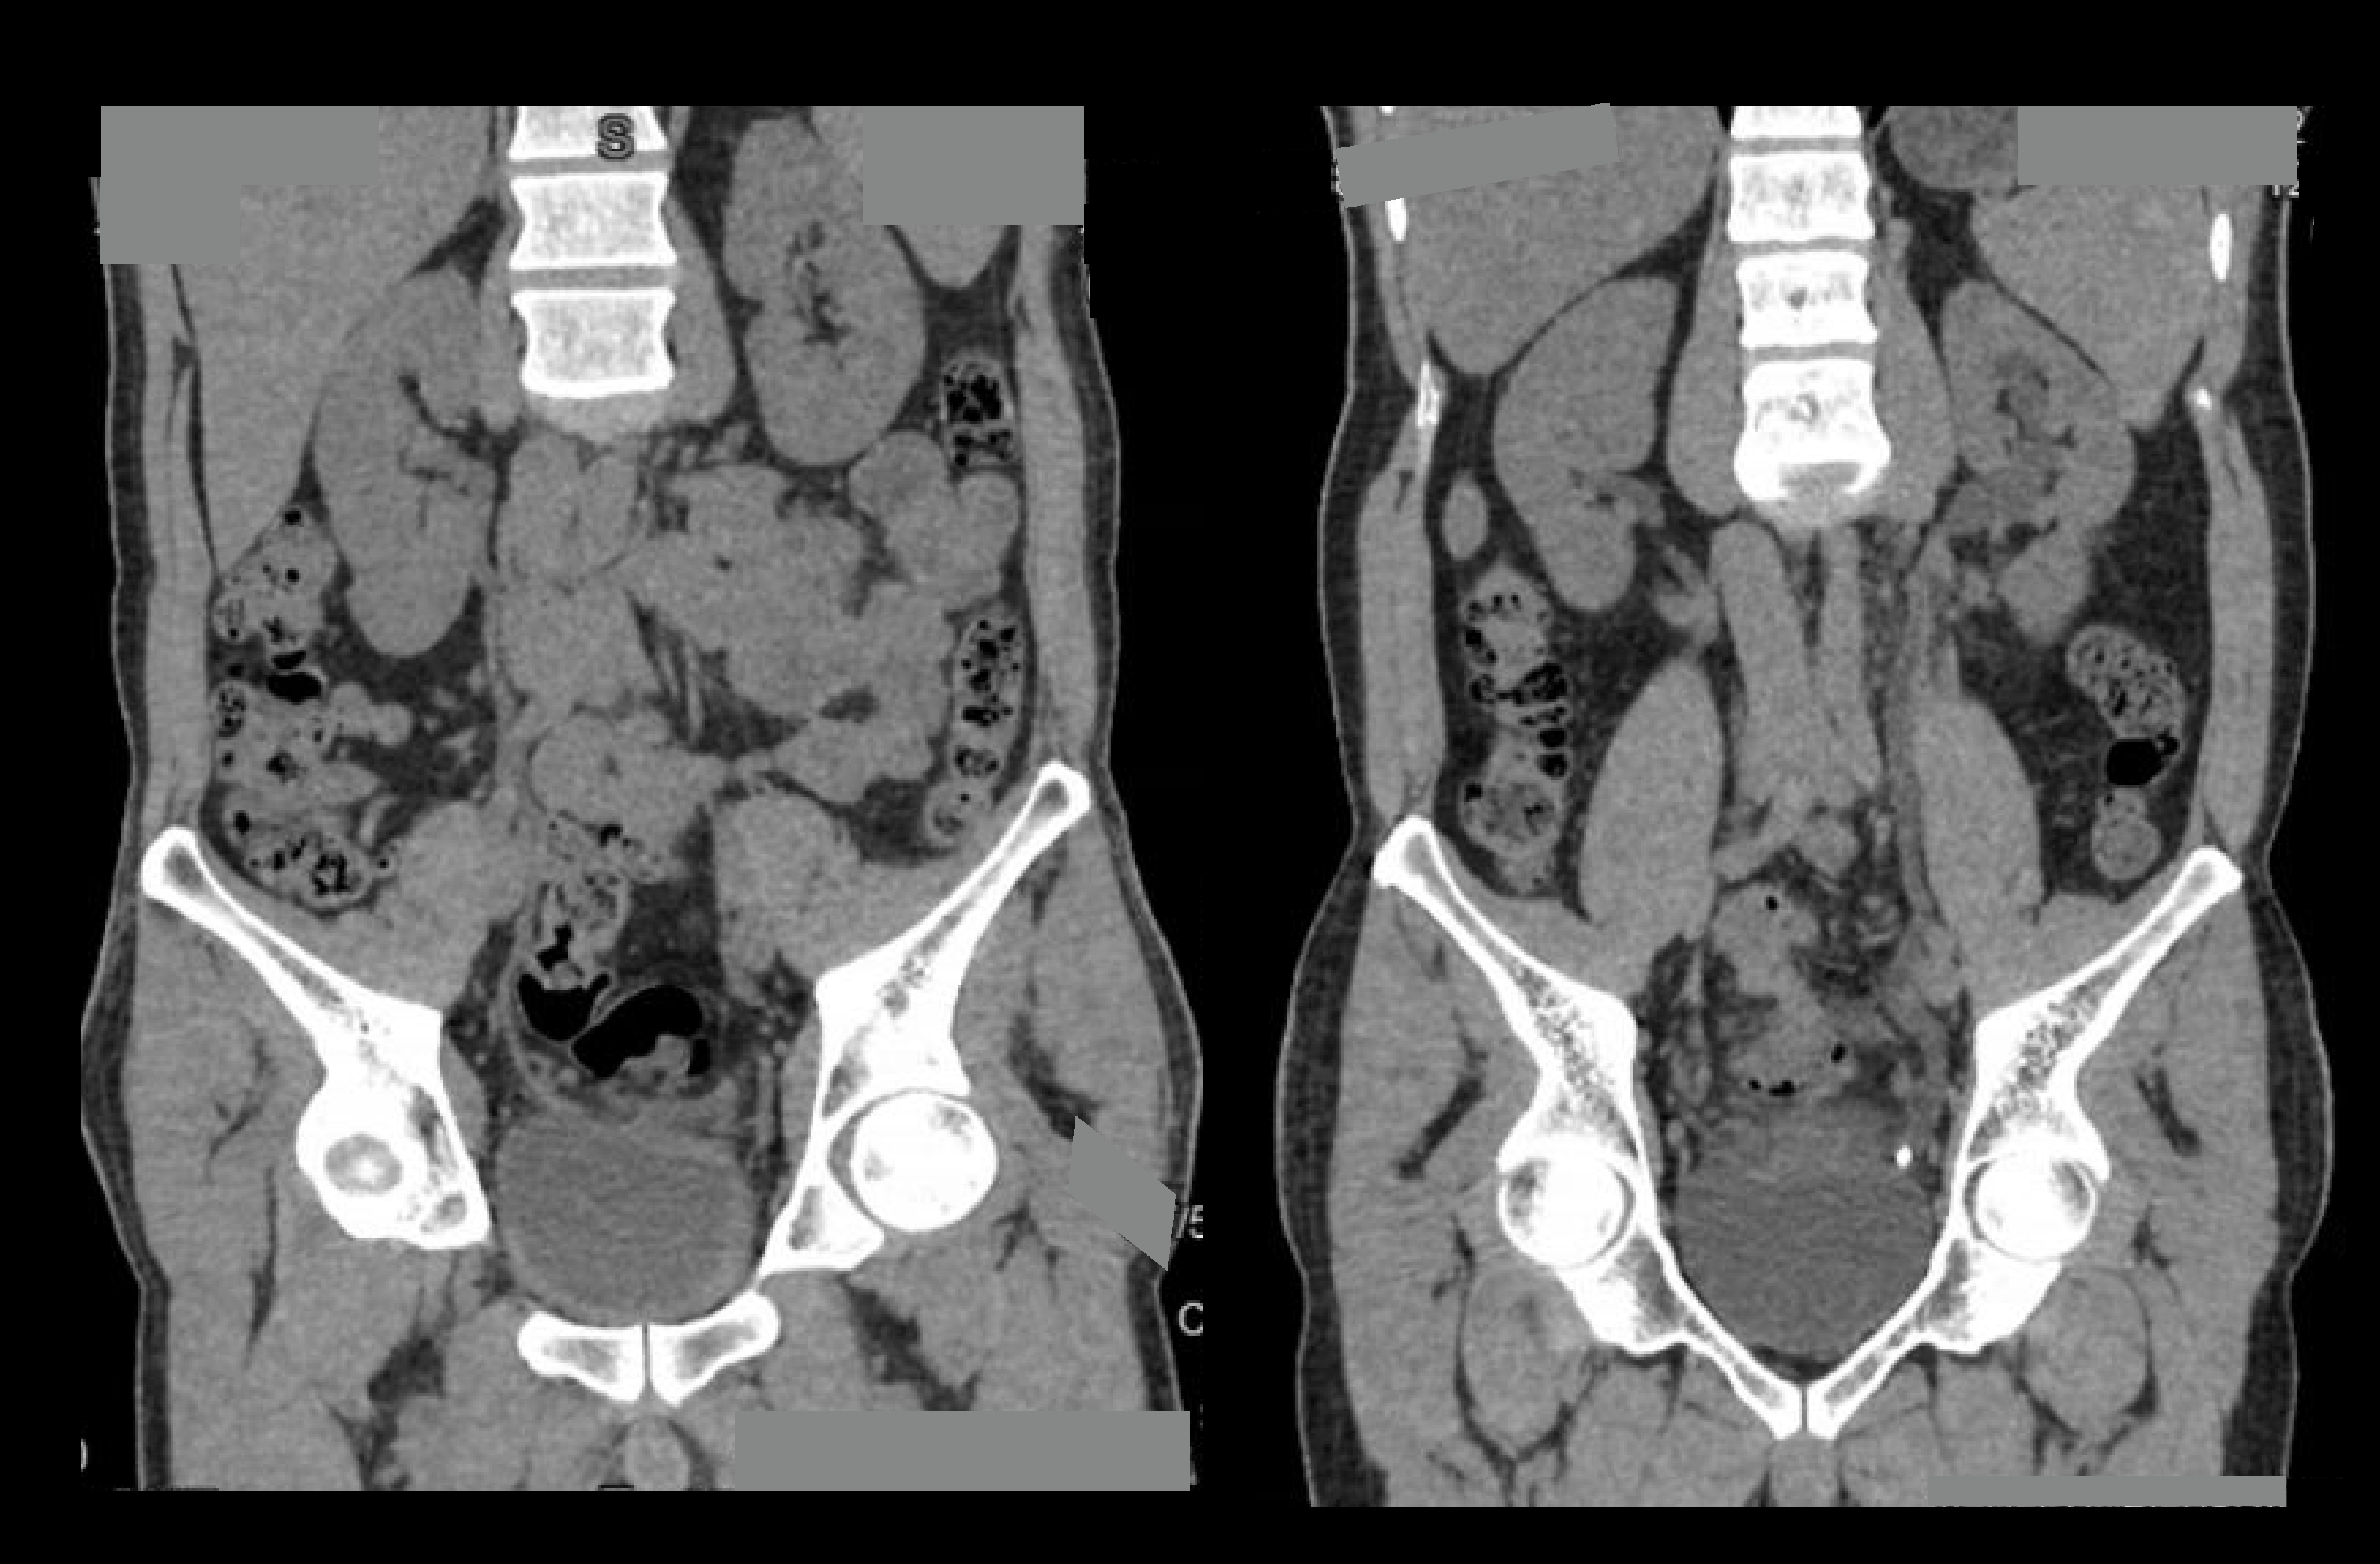

- Multiplanar reconstruction (MPR) images for all phases in soft-tissue window (WW:500, WL:50) with slice thickness ≤ 5mm – refer to non-contrast abdomen scan for images.

- Curved MPR images to show both ureters.